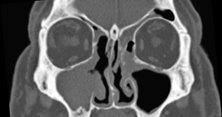

Based on the diagnosis, the patient underwent further surgical intervention. The pre-operative contrast enhanced CT scan revealed extensive residual mass on right maxillary sinus with minimal residual mass on the left maxillary antrum margin extending to the middle ethmoid through the surgical defect (Figure 2). Both frontoethmoidal recesses were filled with soft tissue mass while the rest of the sinuses were clear. Further surgery was carried out when right nasal cavity and antrum were found to be completely obliterated by polypoid tissue. Complete maxillary sinus clearance was achieved with endoscopic partial medial maxillectomy combined with canine fossa puncture. On the left side middle turbinate mucosa had several small polyps and left maxillary antrum macroscopically appeared clear. The histological examination of specimens from both nasal cavities revealed inverted papilloma with no epithelial dysplasia or malignancy. The patient remained under clinical surveillance and in year 2008 bilateral small nasal polyps were noted and further investigated by CT scan that demonstrated soft tissue mass filling right maxillary sinus and extended medially through surgical defect of medial maxillary sinus wall (Figure 3). The left sided nasal cavity did not reveal any suspicious features. He underwent right revision FESS and the histology showed IP in the specimen excised from the floor of right maxillary sinus.

Figure 2 Residual inverted papilloma (IP) worse affecting the right maxillary sinus (Year 2005).